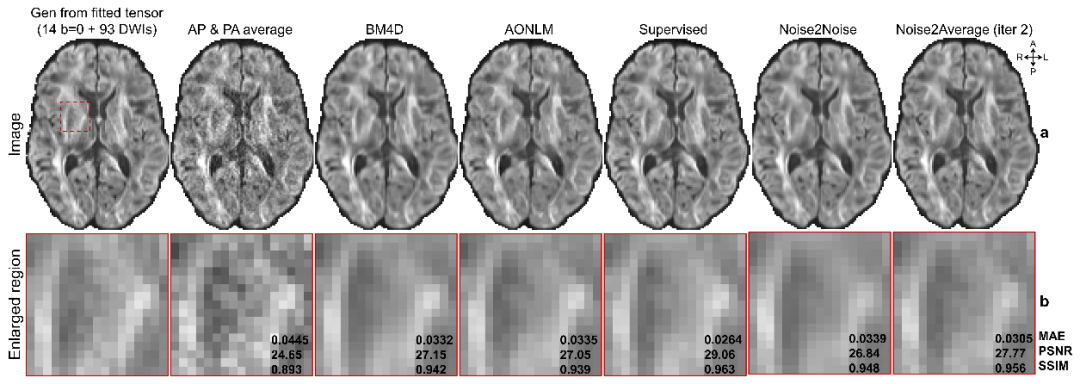

实验结果有力证实了 Noise2Average 的卓越鲁棒性与泛化能力。无论是在高加速 T1 加权成像,还是在复杂的多通道弥散磁共振数据中,该算法均实现了出色的降噪效果,并显著提升了下游微结构定量分析的精度。尤为关键的是,作为一种自监督方法,其性能已逼近监督学习的理论基准,充分确立了该框架在多模态 MRI 去噪及定量成像中的核心实用价值。

提高弥散磁共振成像的图像质量

提高基于弥散磁共振成像的微结构定量精度